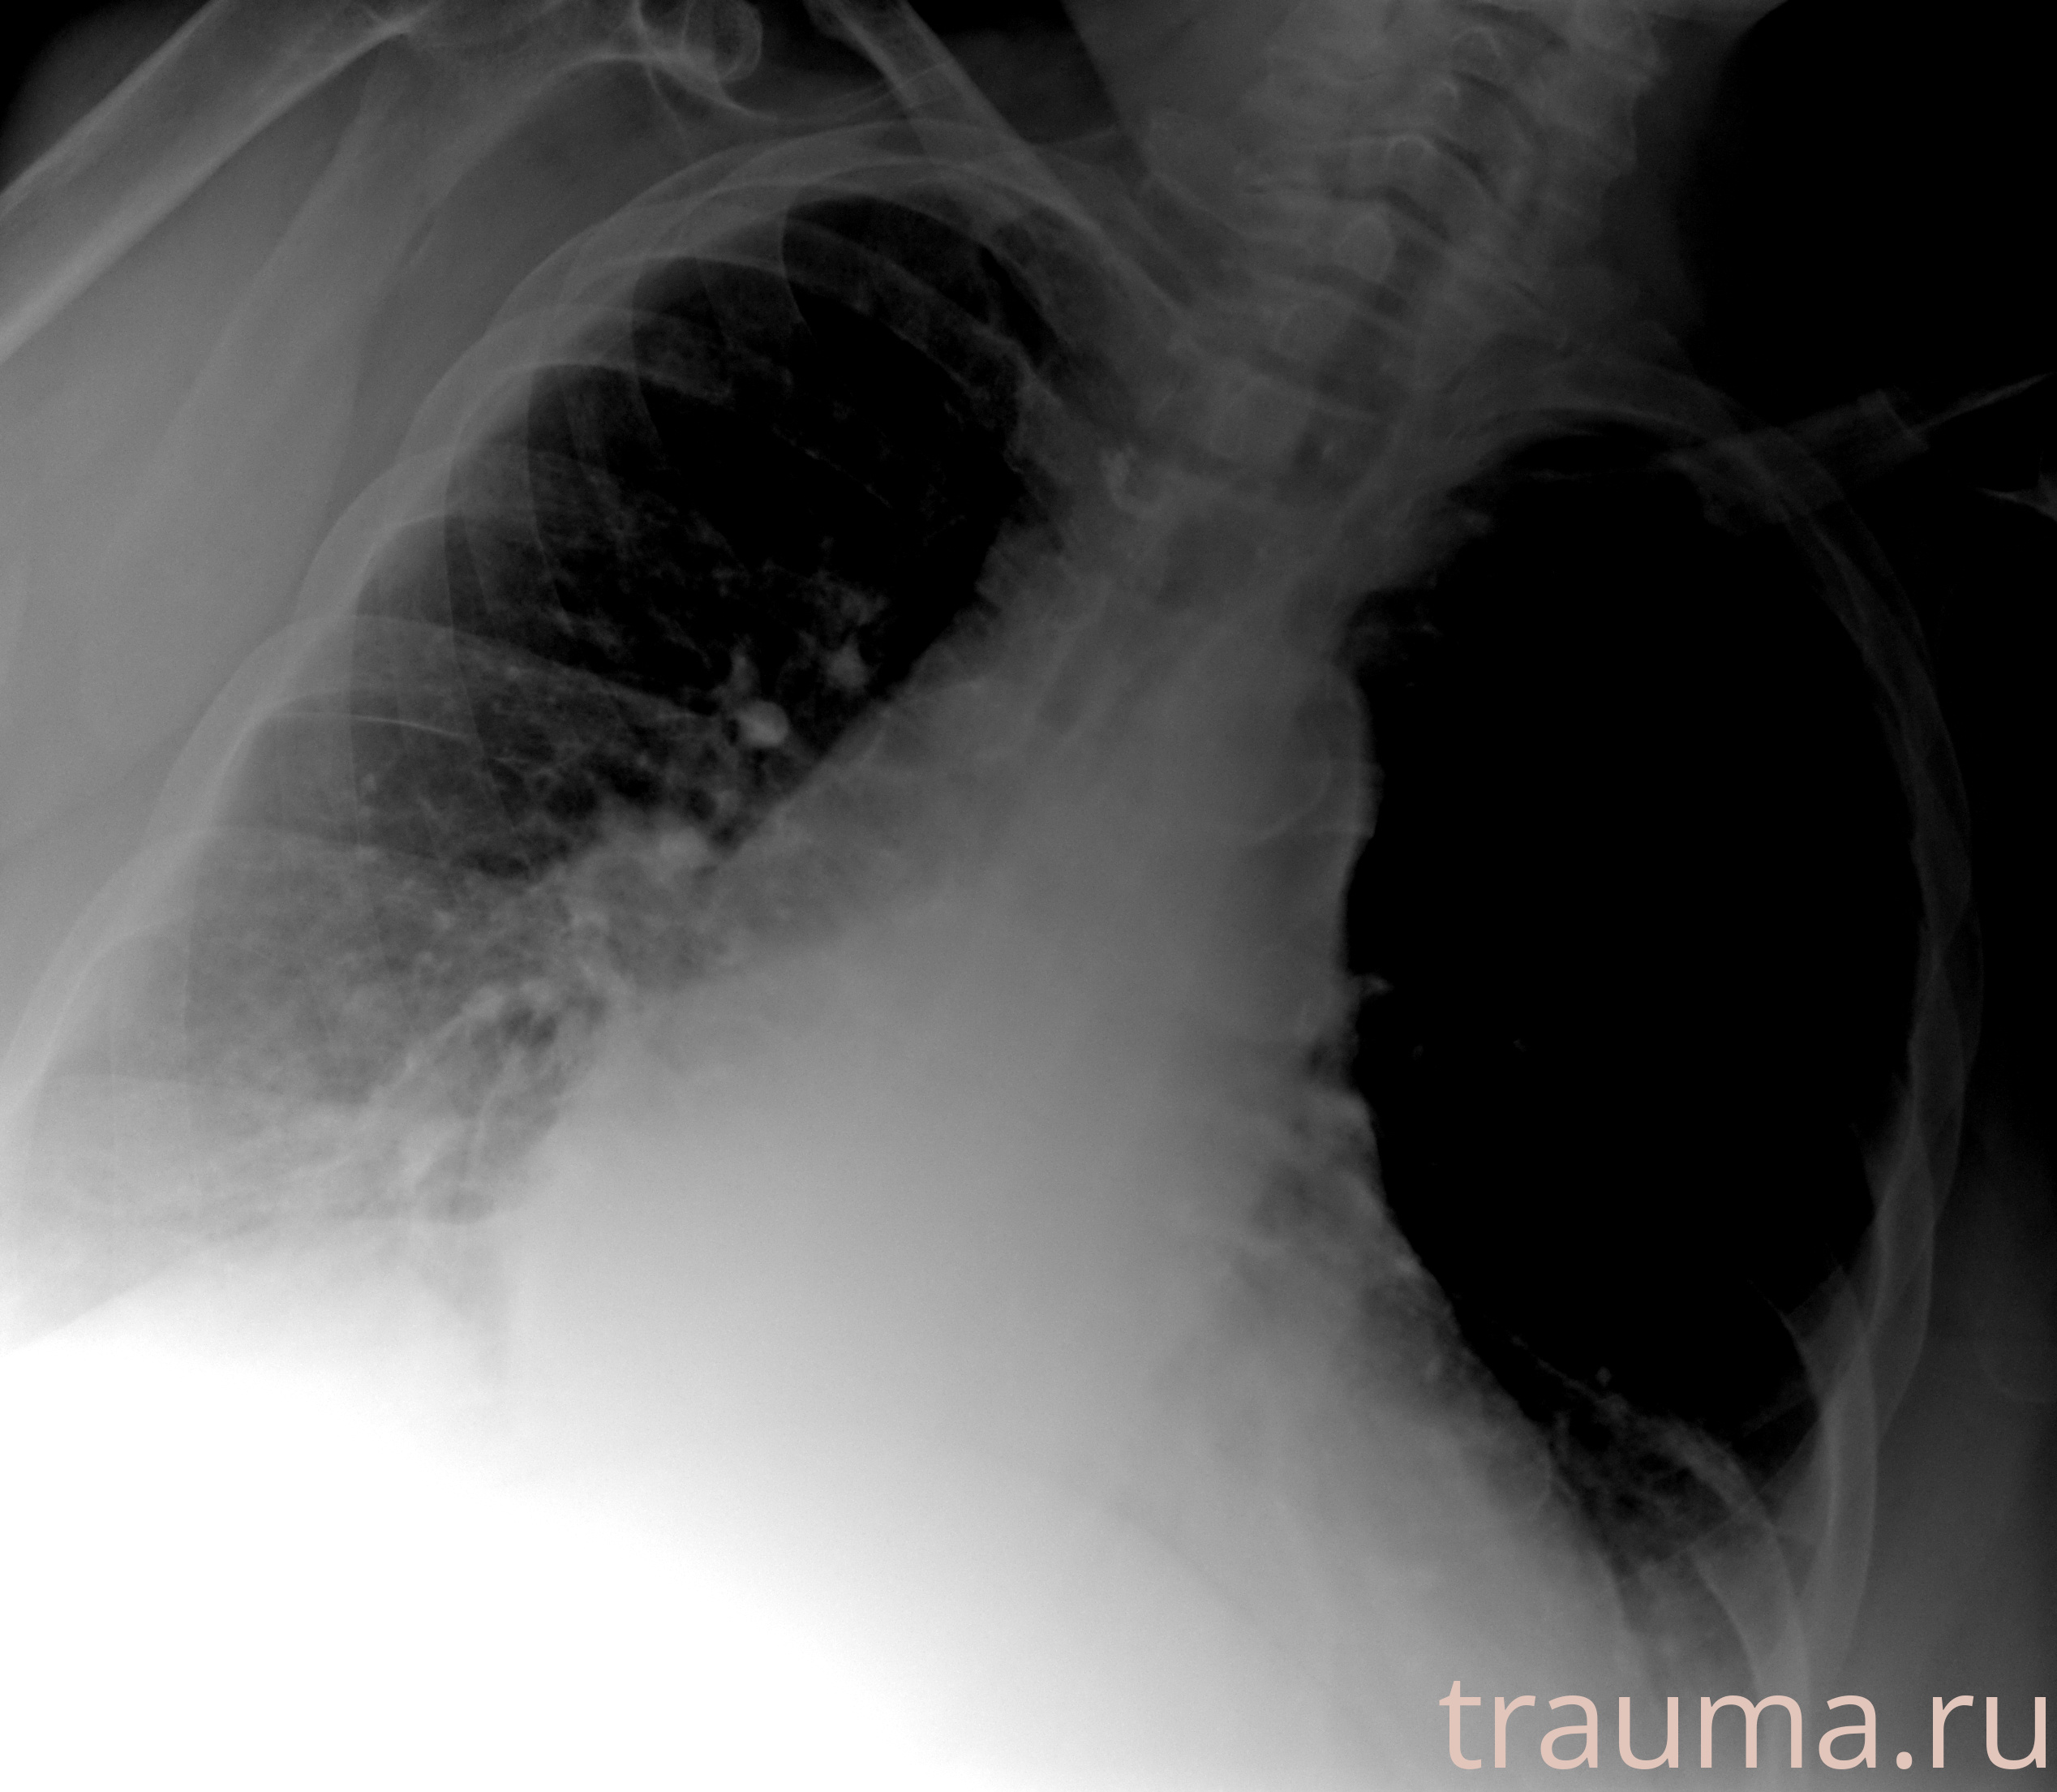

Рентгенограммы

Рентген на дому: по вашему адресу приезжает врач-рентгенолог, травматолог-ортопед с мобильным рентгеновским аппаратом, проводит диагностику травмы или заболевания, делает необходимые рентгенограммы, дает рекомендации по дальнейшему лечению. Получить качественные снимки в домашних условиях возможно благодаря уникальной методике, разработанной МосРентген Центром для института  Склифосовского

при переломе шейки бедра и пневмонии от компании МосРентген Центр - партнера Института имени Склифосовского